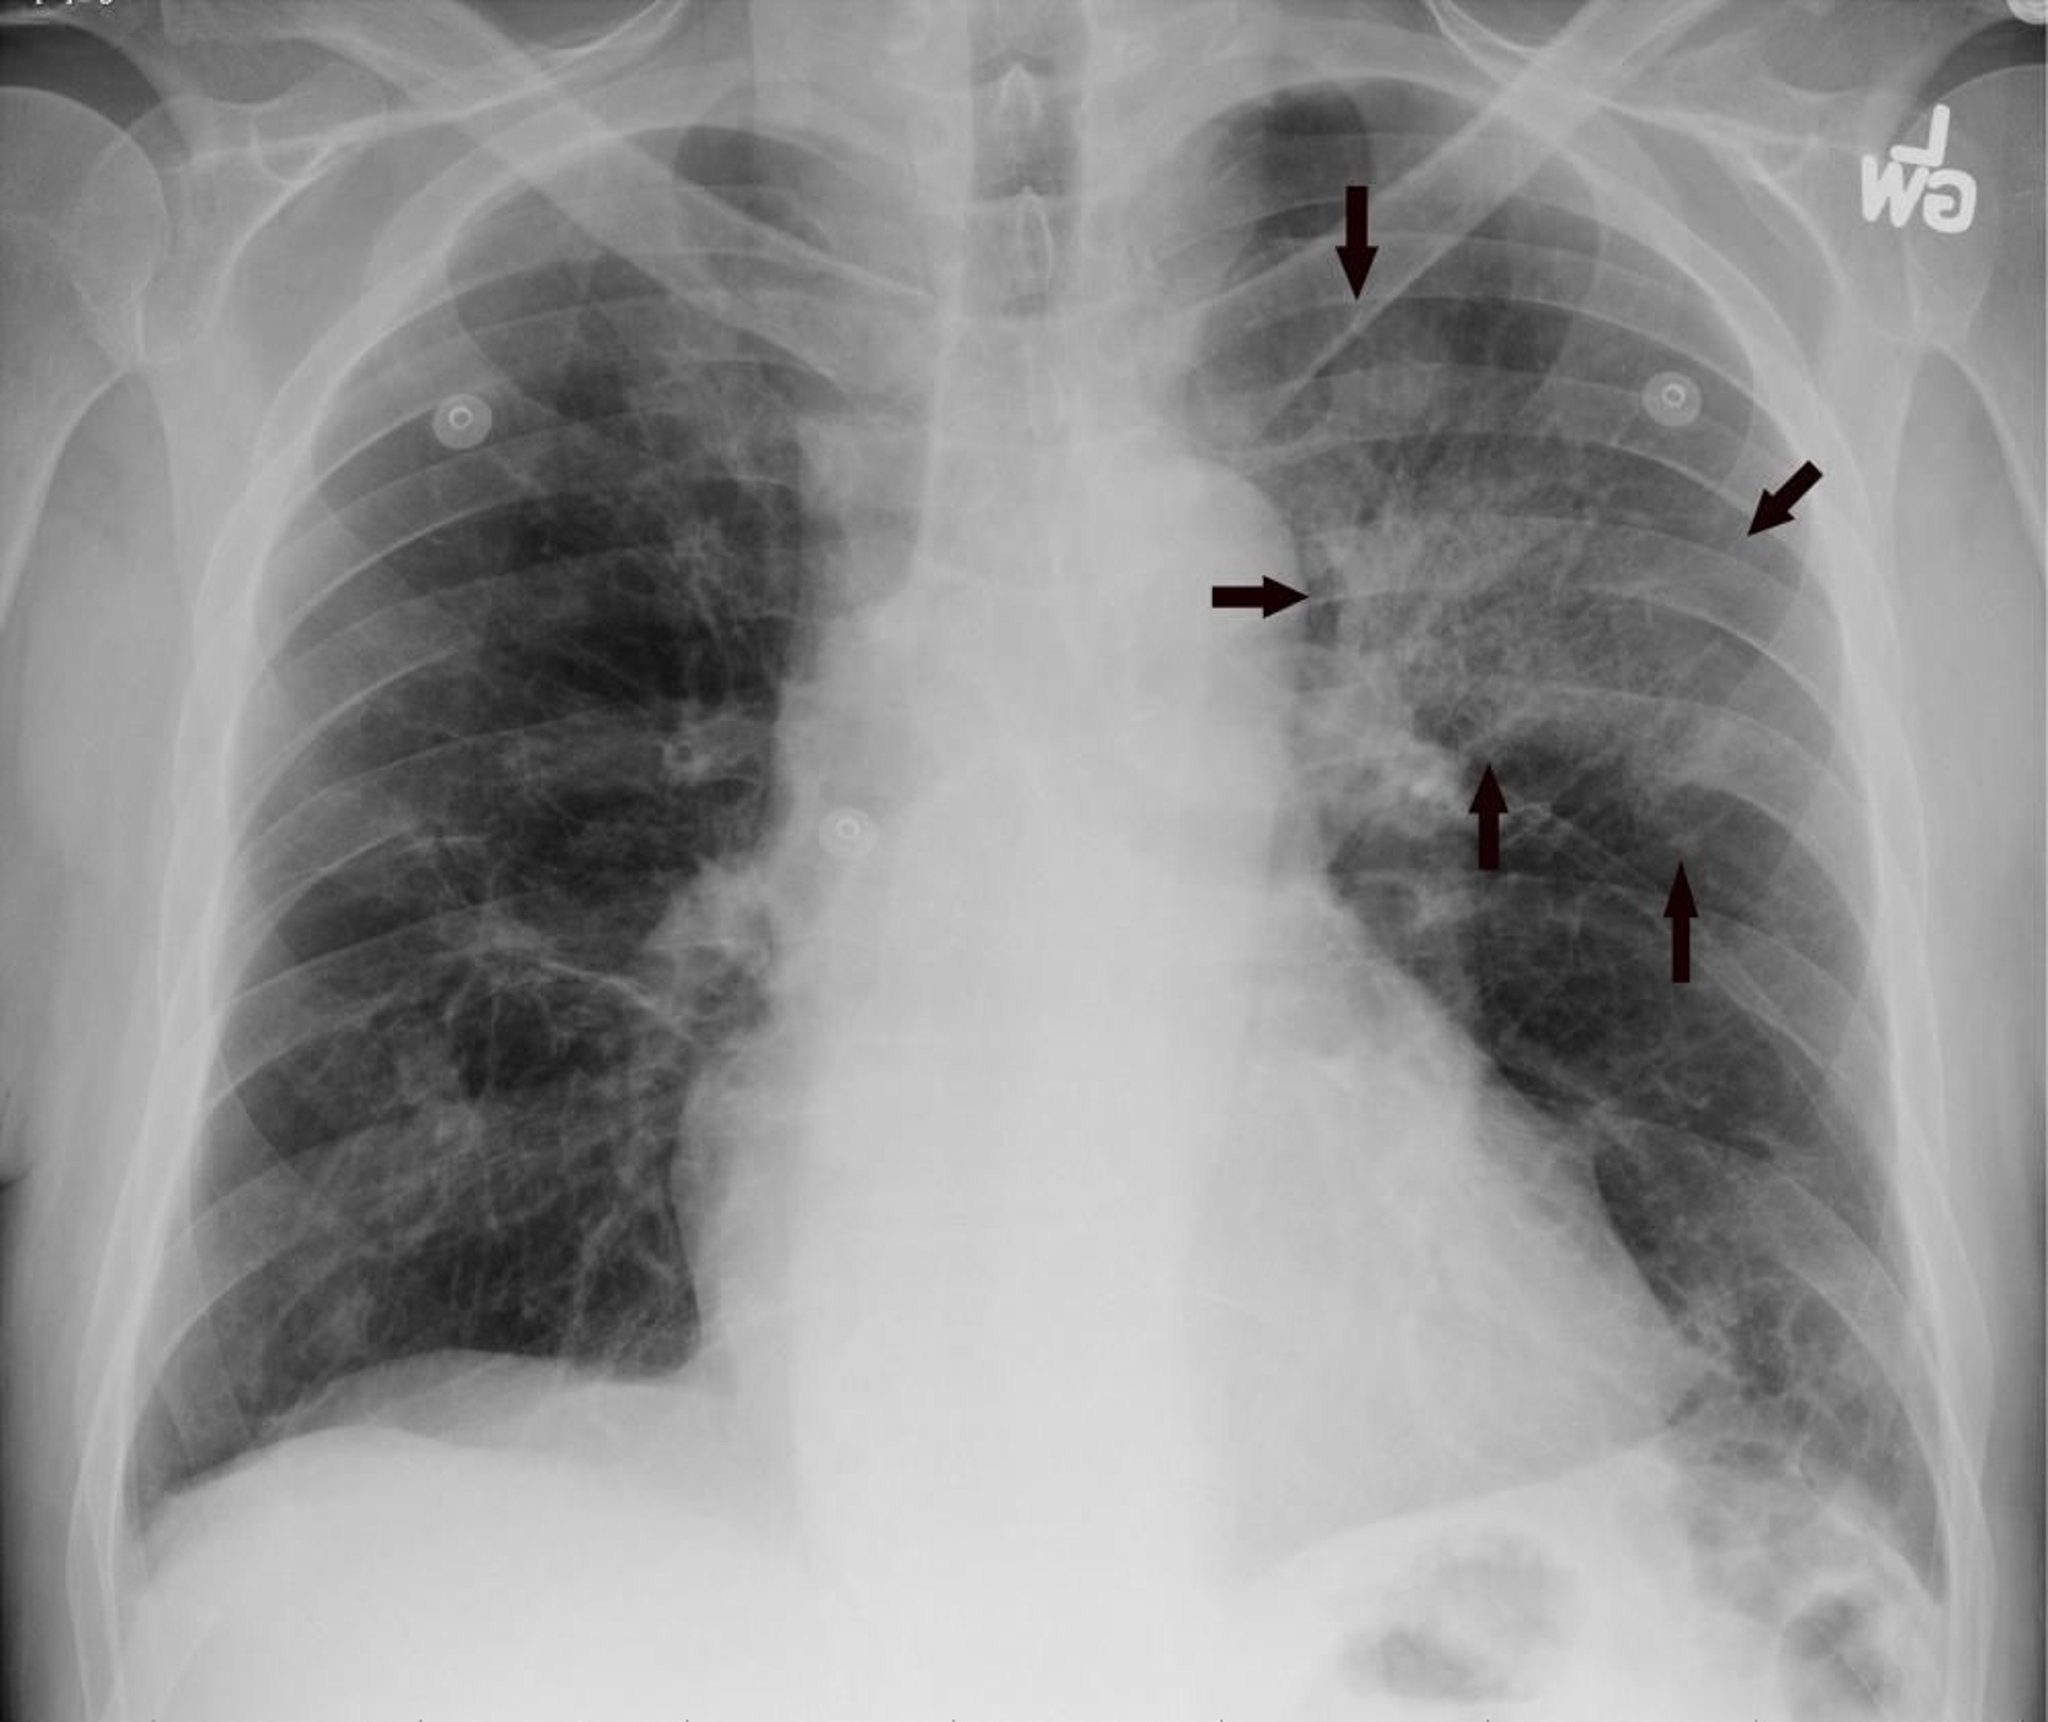

胸部后前位 X 线显示与肺炎一致的左上叶浸润(箭头)。

Image courtesy of Hakan Ilaslan, MD.